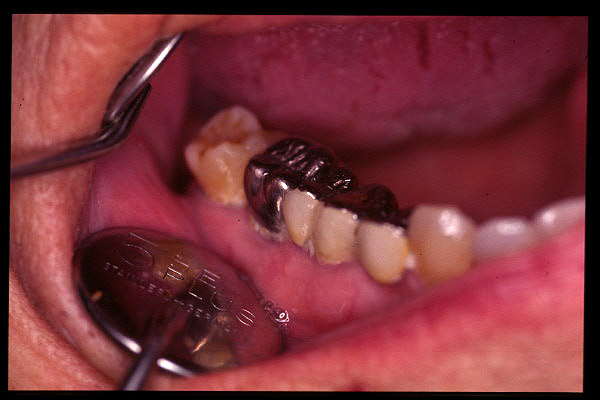

CM Extrusión de molar superior y premolares inferiores por falta de antagonista